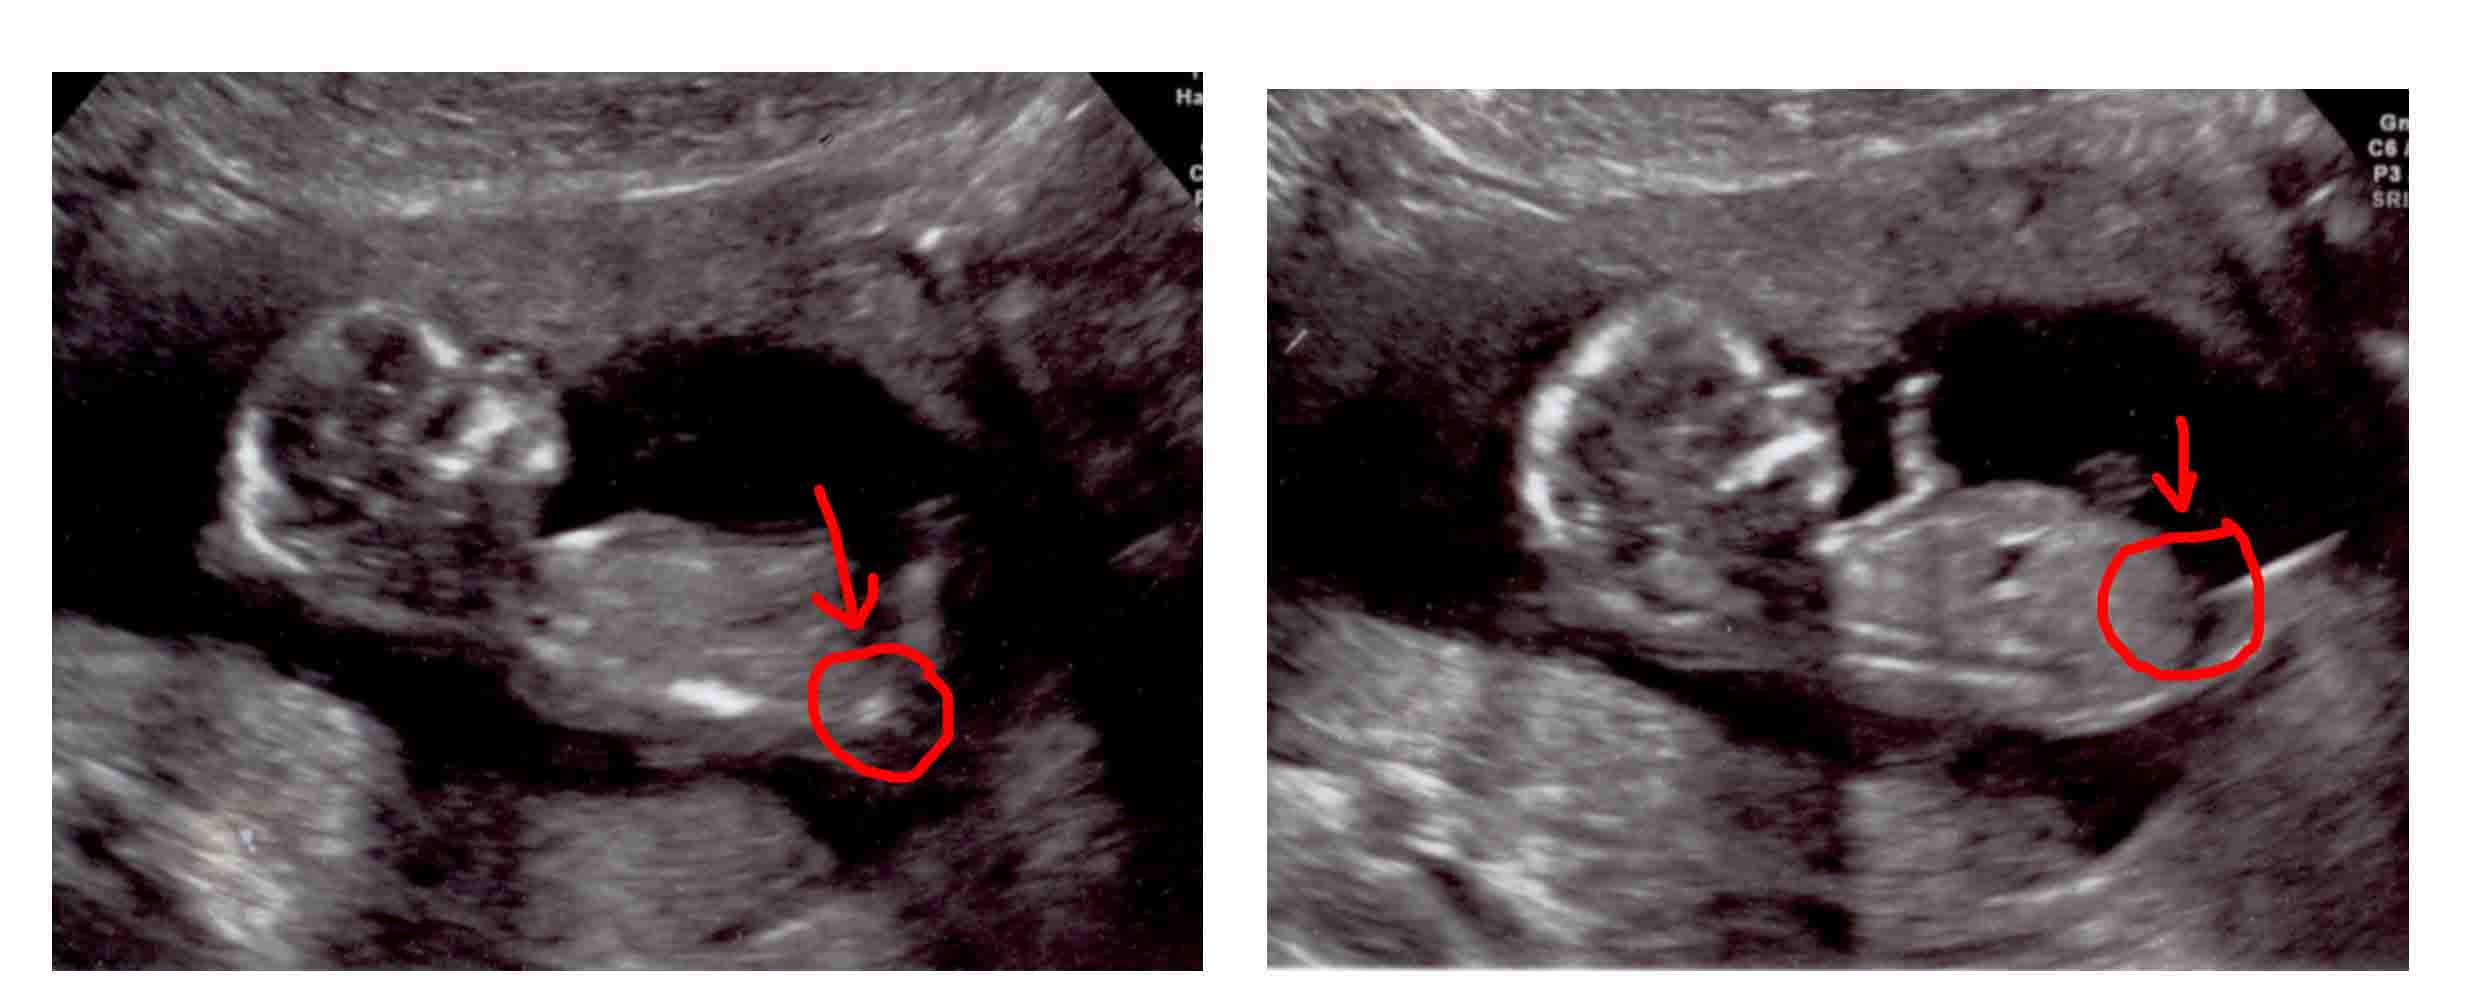

Pleasse have a look and see if you can make a guess - girl or boy :-) xxx

I have had 2 scans so far - one at 12 weeks ( the one face on at the bottom) and the second at 14 weeks (the top 2)

I am desperate to find out if it is a girl or a boy and lots of my friends have had a guess but would love more opinions from the scans if anybody could make a guess from what you can see .......